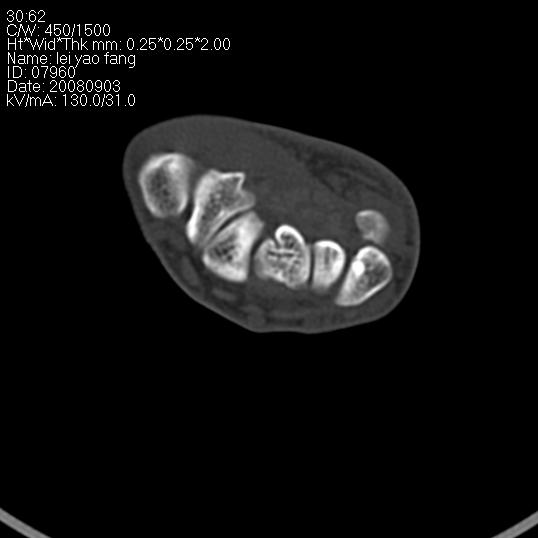

以下是引用杀毒软件在2008-9-4 17:41:00的发言:[br]考虑----舟骨囊肿